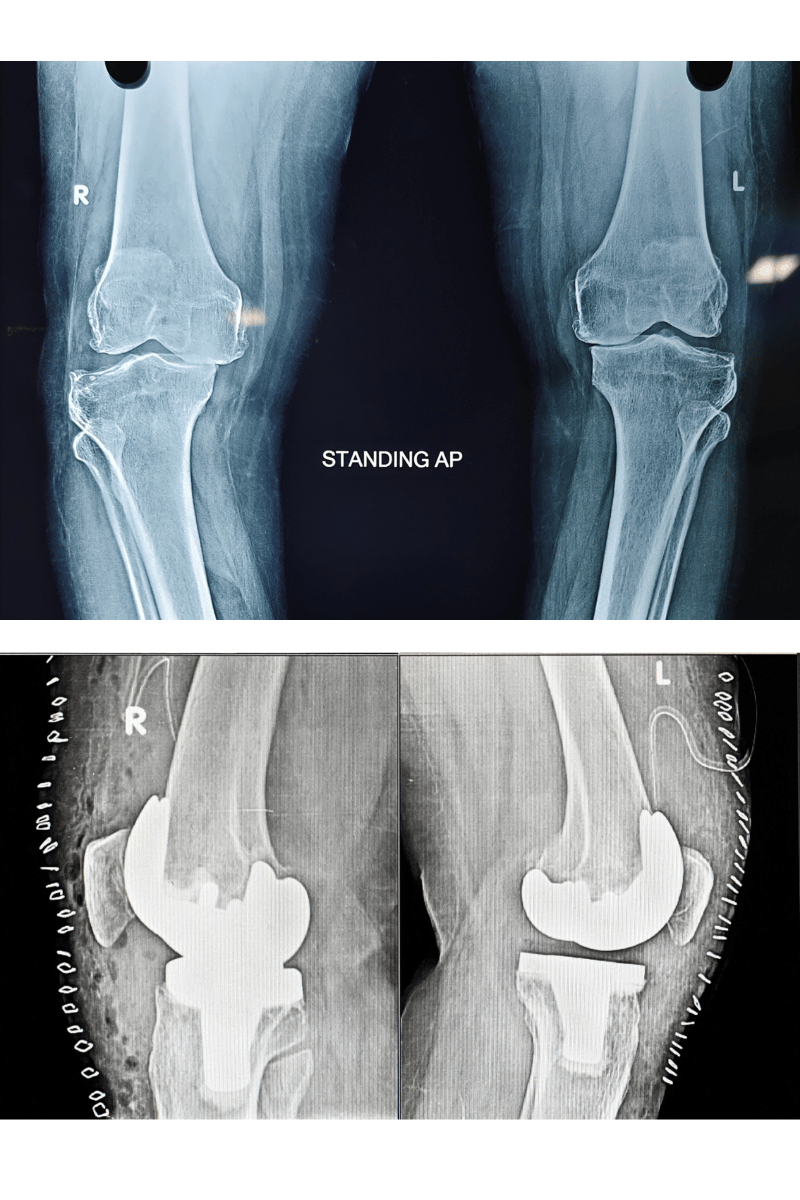

Sivam Hospital – Advanced Knee Replacement in Chennai

At Sivam Hospital, we specialize in advanced joint replacement surgeries to relieve pain, restore mobility, and enhance quality of life. Our expert orthopedic team uses modern techniques and state-of-the-art facilities to ensure safe procedures and faster recovery.

Knee Replacement – Effective treatment for severe Osteoarthritis, Rheumatoid arthritis, secondary arthritis, inflammatory arthritis and joint damage helping patients regain pain-free movement.

Uni Knee Replacement – A minimally invasive partial knee replacement procedure that preserves healthyportion of the joint and tissue while ensuring quicker recovery.

Total Knee Replacement (TKR) – Comprehensive surgical care to replace the entire knee joint, offering lasting pain relief, deformity correction, improved gait and function.

Revision Total Knee Replacement– Specialized surgery to correct or replace the failed knee implants due to infection or trauma restoring stability and improving function.